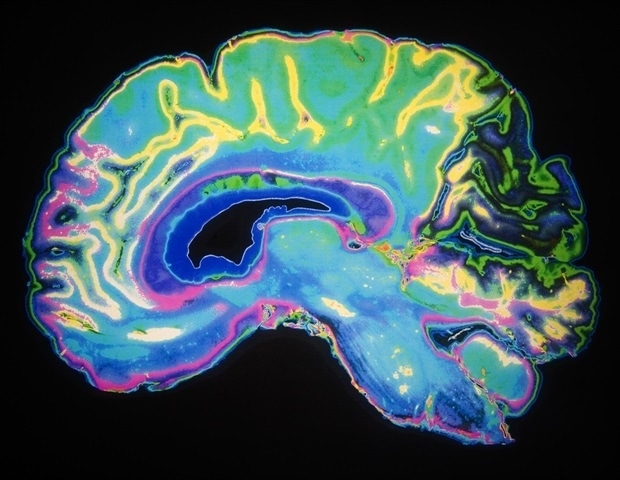

Μελέτη αποκαλύπτει την επίδραση του ύπνου και της ηλικίας στα EEG σήματα του εγκεφάλου

Σε μια σημαντική έρευνα που δημοσιεύθηκε πρόσφατα στο περιοδικό eNeuro, επιστήμονες από το Πανεπιστημιακό Παιδιατρικό Νοσοκομείο της Ζυρίχης εξερεύνησαν πώς η ανάπτυξη του εγκεφάλου και η ηλικία επηρεάζουν τα EEG σήματα που καταγράφονται από ανθρώπους σε κατάσταση εγρήγορσης. Η χρήση ηλεκτροεγκεφαλογραφίας (EEG) είναι γνωστή κυρίως για τη διάγνωση επιληψίας και διαταραχών ύπνου, ωστόσο οι τελευταίες ανακαλύψεις δείχνουν ότι συνδέεται και με άλλες καταστάσεις.